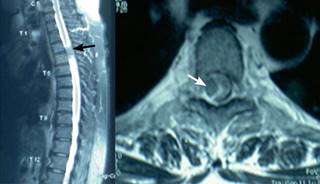

Figura 1: Resonancia magnética de columna torácica ponderada en T2 en plano sagital que muestra: masa ocupativa a nivel de T3-T4 con adelgazamiento de médula espinal (flecha). El corte axial muestra masa ocupativa intraespinal y extramedular que abarca 1/3 del canal medular, presionando la médula espinal hacia la izquierda (flecha).

Femenino de 54 años, con diabetes mellitus tipo dos de siete años de evolución con control irregular con hipoglucemiantes orales, obesidad desde hace 10 años, hipertensa de cinco años de evolución con tratamiento irregular con inhibidores de la enzima convertidora de angiotensina. Canalizada a rehabilitación por medicina general, con diagnóstico de polineuropatía diabética que afecta exclusivamente extremidades pélvicas. A la exploración en rehabilitación: paciente con edad aparente mayor que la real; FC 84 l/min; FR 20 r/min; TA 150/95 mmHg; IMC 33.2. Marcha independiente, lenta, con arrastre de ambos pies; postura con cifosis dorsal, hiperlordosis lumbar, basculación pélvica anterior con abdomen prominente, discreto antecurvatum (10o) de ambas rodillas. Cráneo, cara, cuello al igual que pares craneales normales; abdomen globoso a expensas de panículo adiposo sin visceromegalias, reflejos abdominales disminuidos; genitales normales con control de esfínteres; extremidades torácicas con fuerza muscular 5/5 de manera global, reflejos, sensibilidad y llenado capilar de miembros torácicos normales. El examen clínico muscular de miembros pélvicos mostró: extensores, flexores, abductores, aductores, rotadores externos e internos de cadera con calificación 3/5 de manera bilateral, al igual que cuádriceps e isquiotibiales bilateral; tibial anterior, peroneos, tibial posterior y tríceps sural, al igual que extensores y flexores de los dedos con calificación 2/5; reflejos rotulianos + y aquíleos aumentados +++; sensibilidad hipoestesia vibratoria y táctil discriminativa propioceptiva disminuida en miembro pélvico derecho; con sensibilidad termoalgésica disminuida en miembro pélvico izquierdo; llenado capilar normal, presencia de clonus bilateral agotable; Babinski derecho presente, izquierdo ausente. Con diagnóstico de paraparesia asociada a síndrome de neurona motora superior e inferior, se solicitó resonancia magnética de columna torácica, la cual reveló: tumor intraespinal, extramedular a nivel T3-T4, que ocupa en el corte axial 1/3 del canal medular a dicho nivel. La paciente fue derivada a neurocirugía para valoración y manejo.